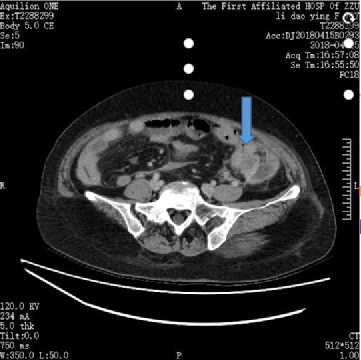

张伟杰教授分享道:恩沃利单抗II期临床研究在我们中心一共入组了16例患者,有3例MSI-H的结肠癌的患者达到了临床完全缓解(cCR),我印象较为深刻的是一位70岁的老年女性,因“结肠癌术后11月、腹壁多发转移4个月”至我院就诊。该患者2018年4月19日肠镜检查诊断为结肠癌,于当月行“腹腔镜下左半结肠癌根治术”,术后病理示:左半结肠中分化腺癌,累及浆膜下层,可见神经侵犯及脉管内癌栓,自检手术切缘未见癌累及,淋巴结未见转移灶。免疫组化结果显示,Ki-67(+>90%)、MLH1()、MSH2(100%+)、MSH6(100%+)、PMS2()。该结果提示,该患者错配修复基因表达有缺失,建议行BRAF基因检测。该患者术后自2018年6月起接受奥沙利铂联合氟尿嘧啶方案化疗,但在2018年11月份复查CT时发现腹壁及腹腔多发结节,考虑转移,判定疾病进展,且腹壁及腹腔病灶无法完全切除。后于当地行放化疗,疗效不佳。

图片

图1.2018年4月15日术前CT